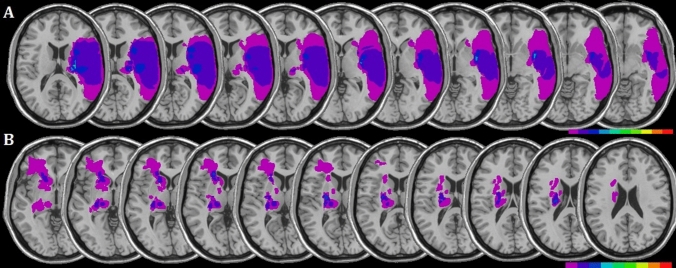

MRI or CT scans were available for all patients. Regions of interest (ROIs) defined the location and the size of the lesion for each patient (Fig. 1). These were reconstructed by means of a template technique, by manually drawing the lesion on the standard template from the Montreal Neurological Institute (Rorden and Brett 2000), on each 2D slice of a 3D volume. Figure 1 shows the overlay lesion plot of all patients. Mean lesion volumes were 33.57 cc3 (± 62.41 cc3, range = 0.3–165.9 cc3) for patients with right brain damage, and 4.26 cc3 (± 4.76 cc3, range = 0.8–16.1 cc3) for patients with left brain damage.

Fig. 1.

Lesions of patients. Overlay lesion plots for patients with a right-sided (A, N = 10) and left-sided (B, N = 9) brain damage. Each colour represents 20% increments, from red areas indicating maximum overlap, to pink areas indicating minimum overlap